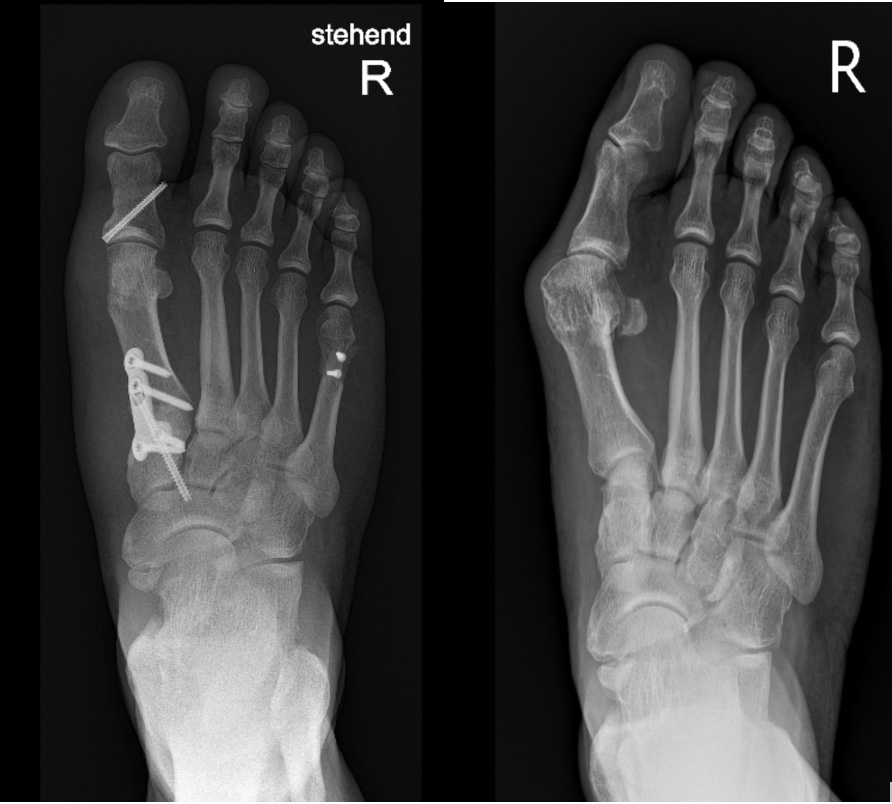

Hinweis zur Abbildung

Hier wird in einem nächsten Schritt eine prä- und postoperative Röntgenaufnahme integriert, welche die kombinierte Korrektur des Spreizfusses mit Hallux-valgus- und Digitus-quintus-varus-Operation veranschaulicht.